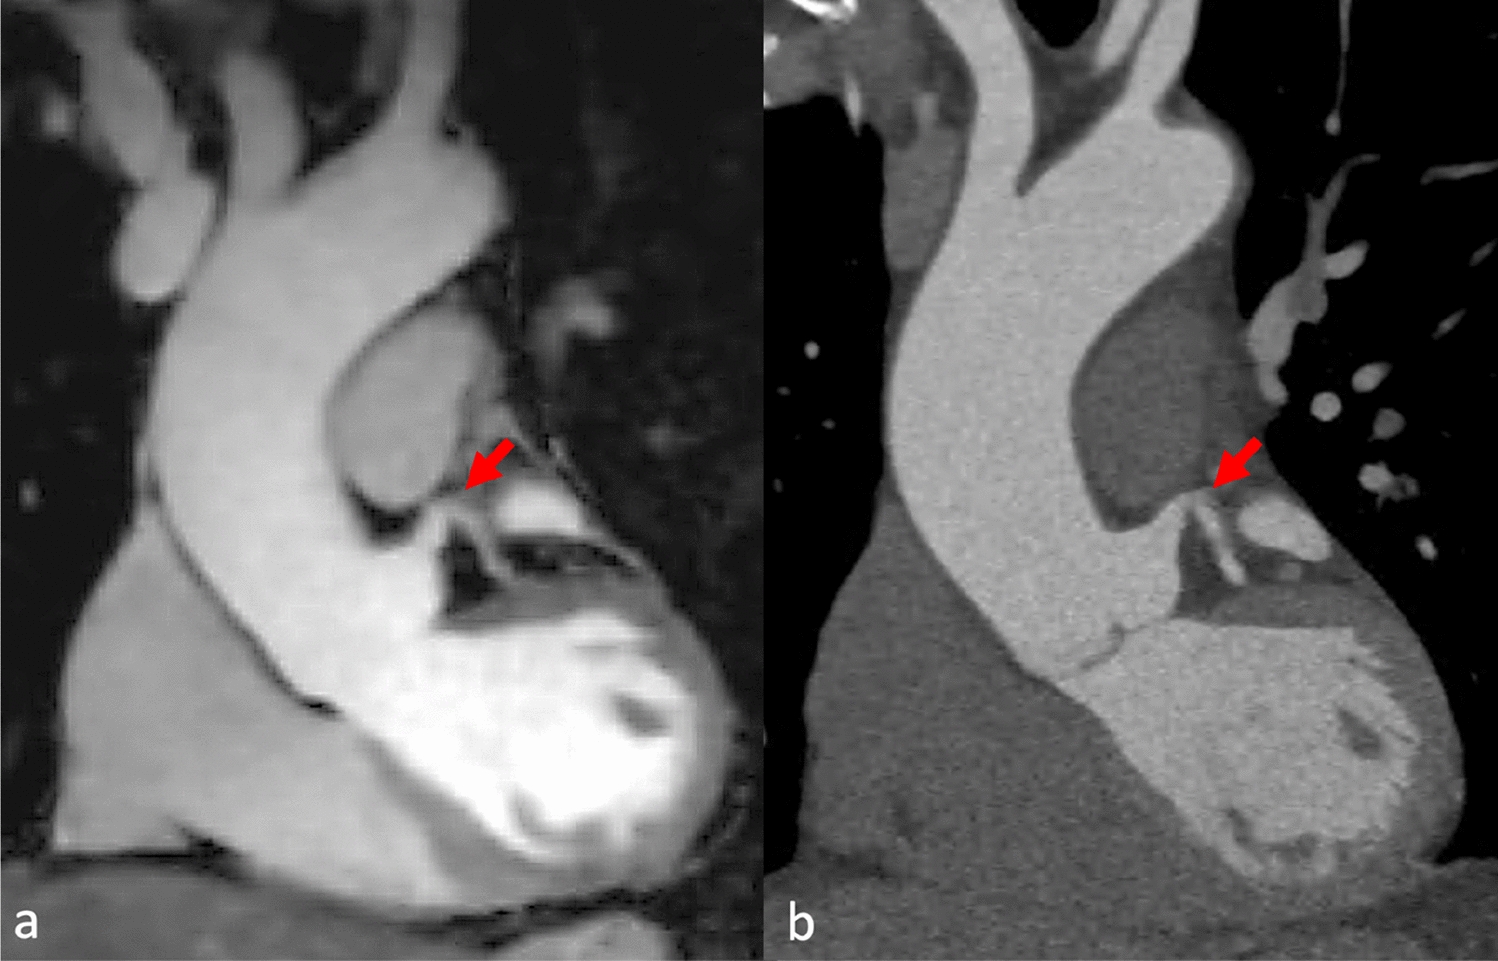

Fig. 3

A patient had an unclear structure at the aortic root noted in the echocardiography. The initial CT scan was performed to confirm the findings, but it did not reveal any abnormalities. Coronal reformation of MRA (a) and CTA (b) of the aortic root and ascending aorta. Excellent depiction of the proximal left coronary artery (arrow)